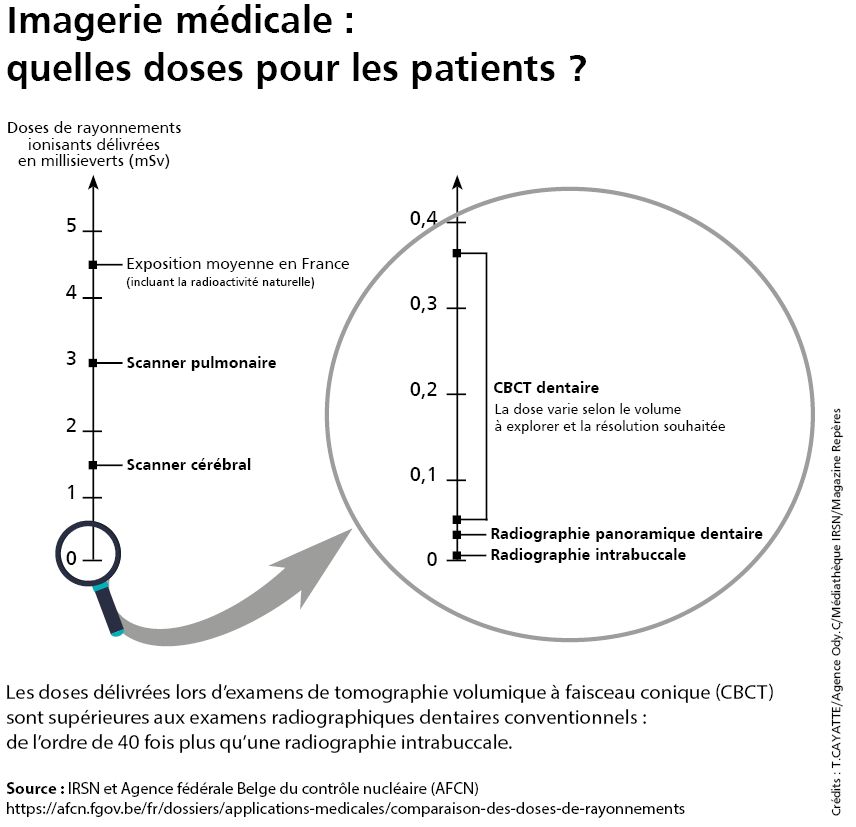

Beaucoup de cabinets dentaires sont équipés d’appareils de tomographie volumique à faisceau conique (Cone Beam Computed Tomography, ou CBCT en anglais). De quoi obtenir des images en 3D complémentaires et de meilleure qualité que celles que fournissent les examens radiographiques jusqu’alors pratiqués par les chirurgiens-dentistes. Les références de dose délivrées aux patients, ou niveaux de référence diagnostiques (NRD), proposés par l’IRSN permettront aux médecins d’améliorer leurs actes.

"L’intérêt croissant, depuis une dizaine d’années, des chirurgiens-dentistes pour la tomographie volumique à faisceau conique est lié à la qualité des images obtenues avec ces équipements radiologiques de pointe installés dans leur cabinet. Celles-ci sont en trois dimensions, comme les scanners réalisés en centre radiologique, mais de meilleure résolution (jusqu’à moins de 0,1 mm). Toujours comparées à celles des scanners, elles sont obtenues avec un niveau plus bas de dose de rayons X délivrés aux patients, même si celui-ci est parfois bien plus élevé que pour les panoramiques dentaires et les radios intrabuccales classiques.

La tomographie volumique à faisceau conique (CBCT) est un examen radiologique dentaire courant. Mais pas toujours utilisé selon les bonnes pratiques. Deux paramètres peuvent faire varier d’un facteur 1 à 6 la dose de rayonnements délivrée au patient : la taille du champ (le volume d’acquisition de données) et la résolution (la finesse des détails observables). Les praticiens doivent les adapter selon les besoins de l’intervention.